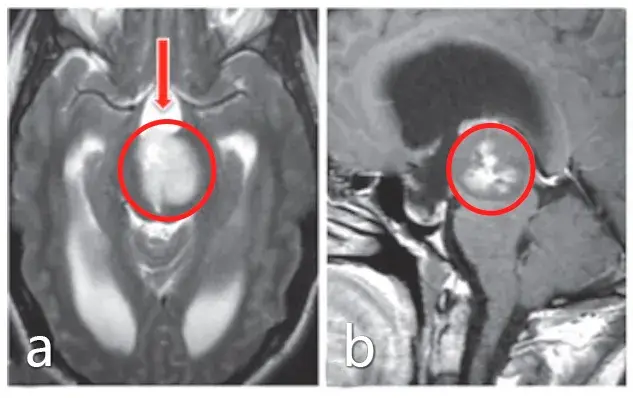

一年多前,10岁的安格因呕吐被查出第四脑室肿瘤,在接受分流术后的第5天,安格被再次推入手术室,成功全切了肿瘤,病理报告显示为低级别胶质瘤。然而安格一家看似有惊无险的治疗之路,...